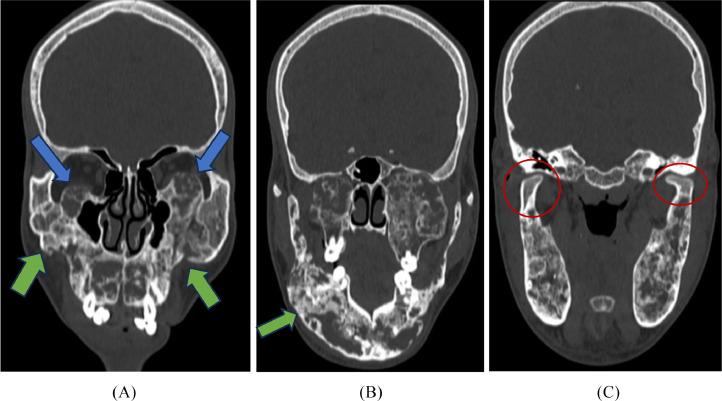

Cherubism is an autosomal-dominant disorder that commonly affects young patients. Our patient a 17-year-old male presented with bilateral nontender swelling over the mandibular area and maxillary area which was insidious in onset and progressive. The diagnosis was made based on clinical and radiological features. Computed tomography of the head in bone window shows multiple lytic sclerotic expansile lesions with coarsened bony trabecular pattern giving the soap bubble appearance of bilateral mandible and maxilla. Surgical intervention was done and upon follow up patient showed drastic improvement. Based on the radiological features grading systems have been developed that help decide the management.

颌骨肥大症是一种常影响年轻患者的常染色体显性疾病。我们的患者是一名17岁男性,下颌区和上颌区出现双侧无痛性肿胀,起病隐匿且呈进行性发展。诊断基于临床和放射学特征。头颅骨窗计算机断层扫描显示多个溶骨性硬化性膨胀性病变,骨小梁模式增粗,双侧下颌骨和上颌骨呈现肥皂泡样外观。进行了手术干预,随访时患者显示出显著改善。基于放射学特征已开发出分级系统,有助于确定治疗方案。